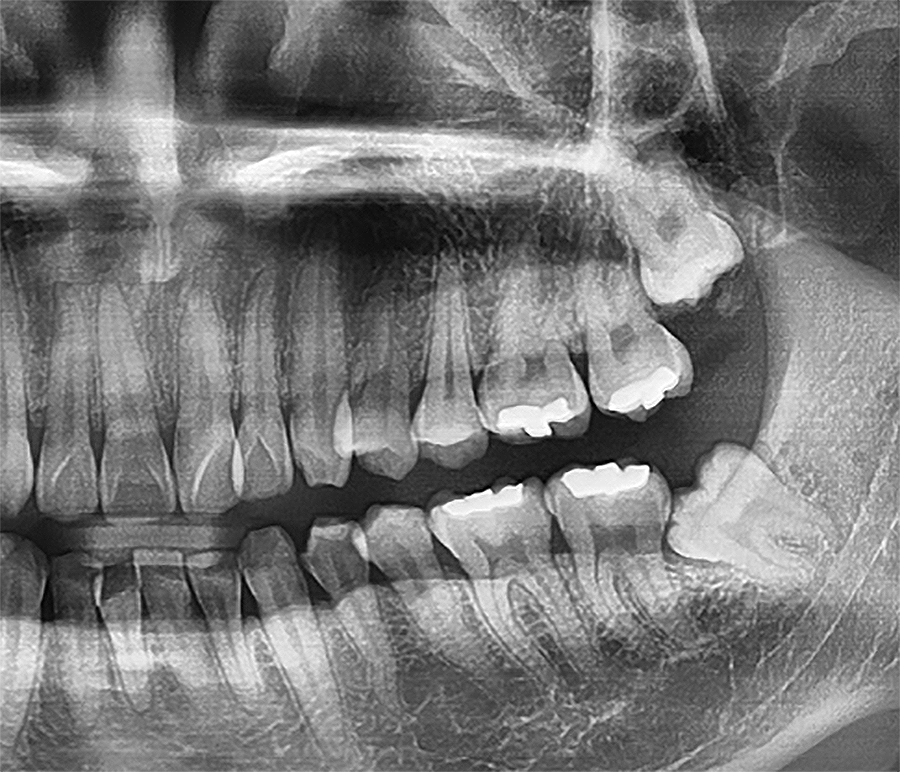

파노라마와 치근단 엑스레이를 찍어봤더니

위아래 양옆 4개를 가지고 있었고,

그 중 왼쪽을 아파해서 그 걸 먼저 뽑기로 결정했죠.

엑스레이를 찍어보니 완전 수평으로 누워있었어요.

딱 봐도 어려워보이는 케이스였죠.